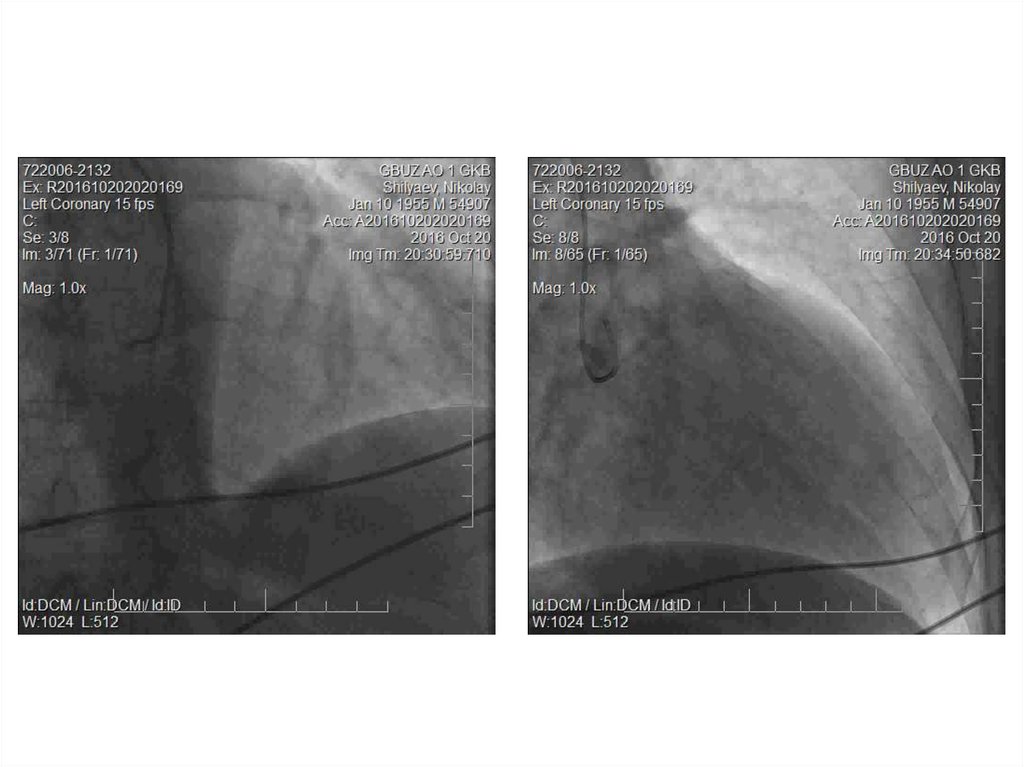

• Пациент Ш., 61 года находился в КХО

ПГКБ с 20.10. по 21.10.16.

• Жалобы на одышку, дискомфорт в ГК в

области грудины при ФН.

• Жалобы с лета 2016 г. Лечился в НЦГБ.

Консультирован в ГКЦ, рекомендована

КАГ.

36.

• КАГ (20.10.16.): тип кровоснабжения сердца –

сбалансированный. ЛКА: ствол, ПНА, ОА – не

изменены. ПКА – не изменена.

• От правого синуса Вальсальвы единым устьем с

ПКА отходит коронаропульмональная фистула

диаметром 4,5 мм (выраженный сброс

контраста в ствол ЛА). От левого синуса

Вальсальвы отдельным стволом отходит

аортопульмональная фистула диаметром 2,5

мм (сброс контраста менее выражен).

37.

• Заключительный клинический диагноз:

ВПС. Аномалия развития коронарных

артерий:

коронаропульмональная

фистула, аортопульмональная фистула.

Трикуспидальная регургитация II ст.

ПБЛНПГ.

Экстрасистолия.

Легочная

гипертензия II ст. ФК СН II (NYHA).

Артериальная гипертензия III ст., риск 4.

Атеросклероз БЦА. Стеноз ЛВСА.

• Показана операция: Эндоваскулярная

окклюзия фистул.